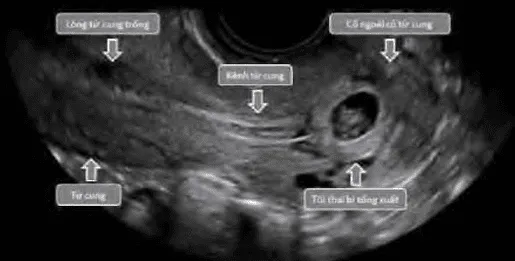

Phần tiêu đề “Sảy thai khó tránh”Ra máu kèm mở cổ tử cung khi thai vẫn còn trong buồng tử cung. Cần phân biệt với thai ngoài tử cung ở cổ tử cung bằng β-hCG và siêu âm.

- Sảy thai khó tránh (inevitable miscarriage).